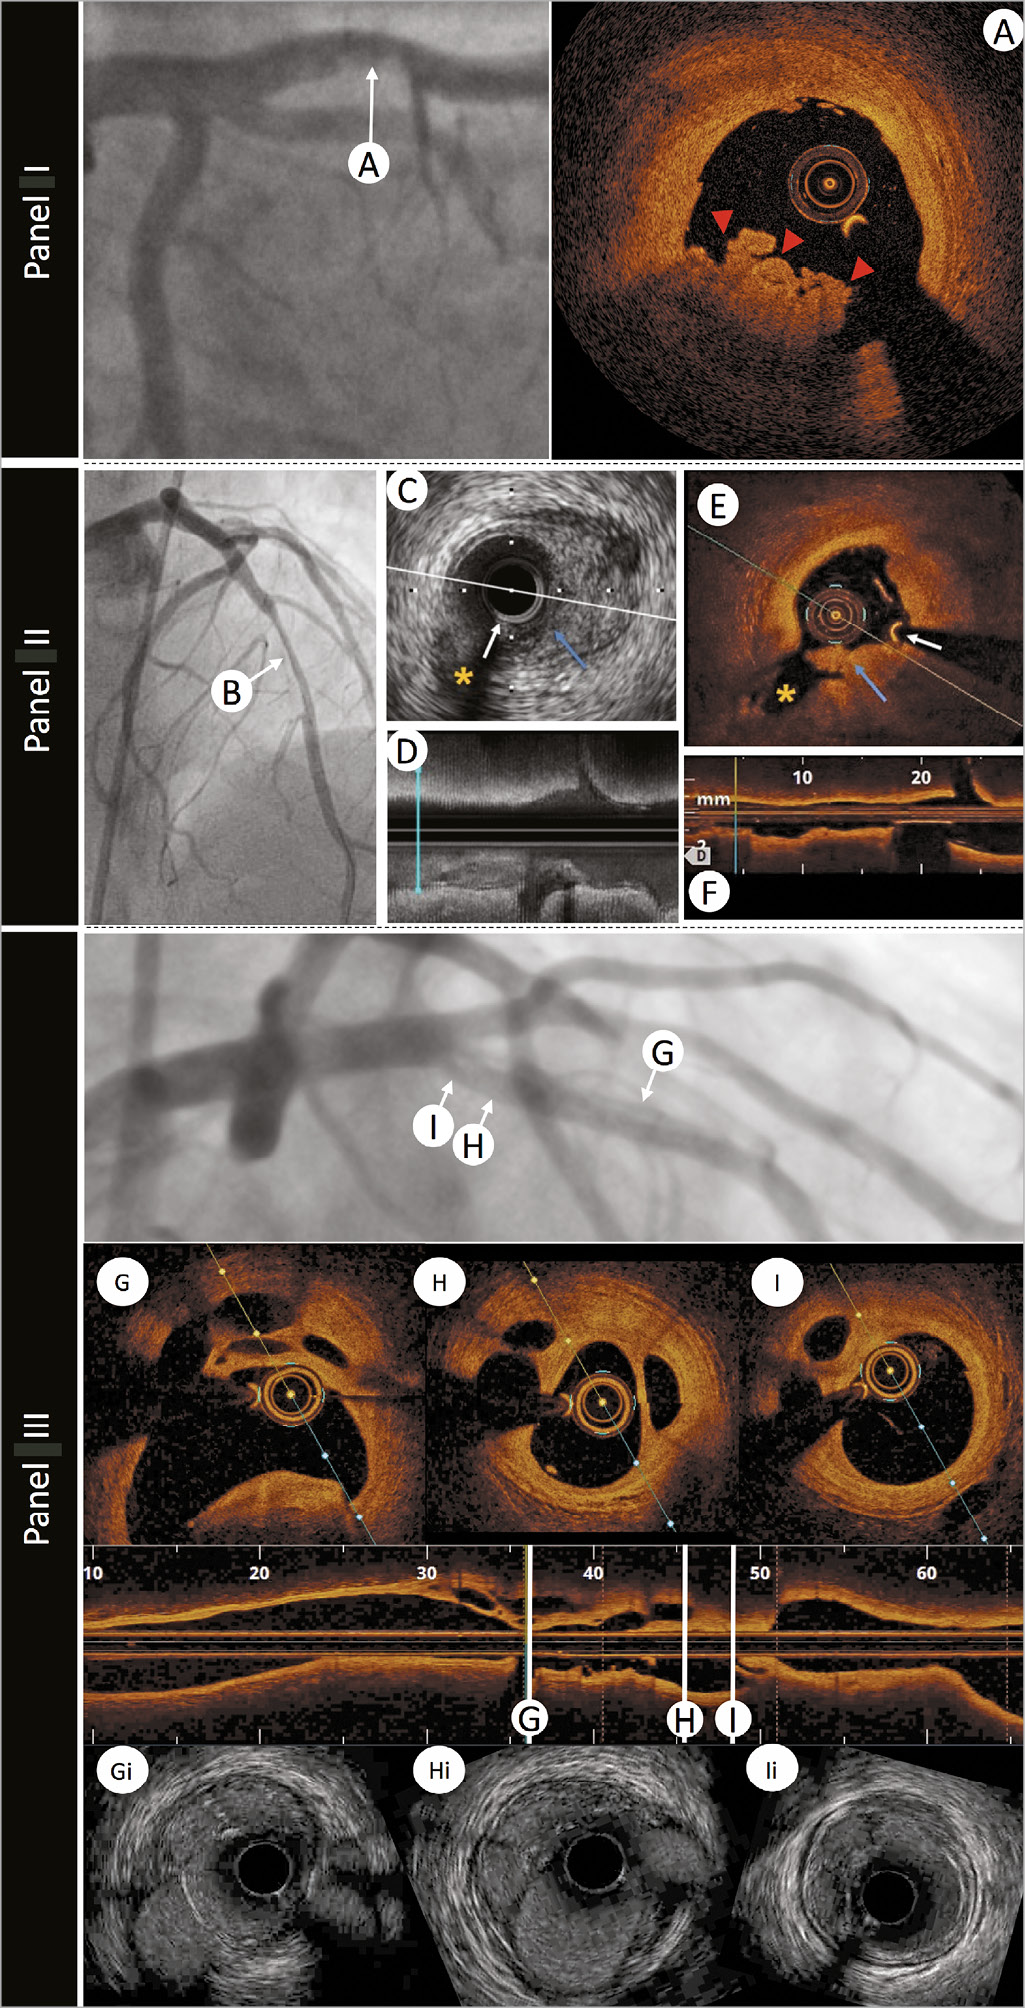

Intracoronary imaging can delineate luminal discontinuity/plaque disruption and associated thrombus, the hallmarks of a culprit lesion. Optical coherence tomography provides accurate detection of intraluminal thrombus14 and is capable of distinguishing red and white thrombus due to the optical attenuating property of red blood cells, abundant within red thrombus (Figure 2 and Supplementary Table 1). Intravascular ultrasound detection of thrombus is more challenging (see Figure 2, Panel 2) but can be improved by stationary imaging at the level of the presumed thrombus and a small injection of contrast to highlight the luminal contour. The advent of high-definition IVUS promises superior resolution and improved diagnostic capabilities, however, at present a data-driven comparison with OCT is lacking.

Figure 2. The role of intravascular imaging in delineating thrombus. Panel I: an angiographic image of a left anterior descending artery in a patient with ST-elevation myocardial infarction presentation and anterior ST-segment elevation. A hazy filling defect is evident in the proximal segment of the vessel, highlighted by white arrow A. Optical coherence tomography image (A) demonstrates red thrombus (red arrows) with an irregular surface and adherent to the lumen, attenuating the light, and obscuring deeper structures. Panel II: a 45-year-old woman was admitted with chest pain and anterior ST-elevation. Emergent angiography revealed a filling defect in the mid-left anterior descending artery. After thrombus aspiration angiography showed a tubular stenosis in the mid-left anterior descending artery (B) that was investigated with intracoronary imaging to determine the substrate of the acute coronary syndromes. Corresponding intravascular ultrasound and optical coherence tomography images are shown. (C and D) Cross-sectional and longitudinal intravascular ultrasound images (40 MHz) demonstrating the presence of atherosclerotic plaque (visible in C from 2 to 6). Intraluminal material protruding towards a small side branch was visible (blue arrow). Optical coherence tomography (E and F) confirmed the presence of atherosclerosis (with lipid content given the attenuation observed) and demonstrated the presence of white thrombus (irregular mass protruding into the lumen with optical shadow).White arrow indicates the guidewire artefact. Asterisk indicates the side branch used for matching of corresponding cross-sections. Panel III: left anterior descending artery with mid-vessel filling defects secondary to a conservatively managed anterior ST-elevation myocardial infarction 10 years earlier. Longitudinal optical coherence tomography imaging with three representative optical coherence tomography frames (G, H, and I) demonstrating re-canalized thrombus. Matched HD-IVUS (Boston Scientific) images (Gi, Hi, and Ii) demonstrating the superior delineation of structures with light-based imaging.